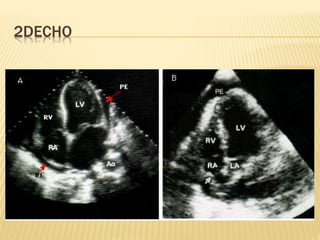

2DECHO

2D ECHO

 Pericardial thickening

 Dilatation of IVC and hepatic veins

 Sharp halt in ventricular filling in early

diastole

 Flattening of left ventricular posterior wall

 Atrial enlargement

2DECHO TAMPONA

DE

CONS.

PERIC.

RESTR.

CM

RVMI

THICKENED PERCARDIUM ------ P ------ -----

PERICARDIAL CALCIFICATION ---- P ------ ------

PERICARDIAL EFFUSION P ----- ----- -----

RV SIZE SMALL N N ENLARG

E

MYOCARDIAL THICKNESS N N INCRE N

RHT ATRIAL COLLAPSE AND

RVDC

P ------ ------- ------

INCREASED EARLY FILLING,

INCREASED MITRAL FLOW

VELOCITY

---- P P P

EXAGGERATED RESP

VARIATION IN FLOW VELOCITY

P P ---- -----